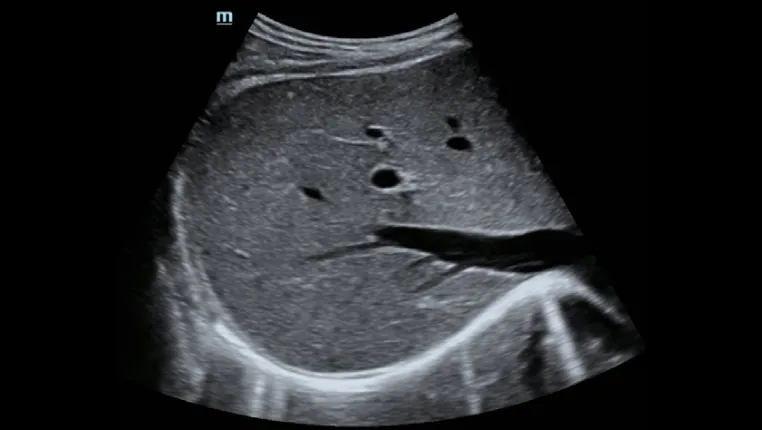

Асцит печени

Оценка морфологии печениЭргономичный дизайн